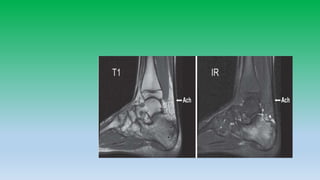

5. T1 mid sagittal image shows sharp interface b/w the normal bright kagers fat pad and normal uniformly dark Achilles tendon. Mid sagittal inversion recovery image revales no abnormal signal intensity in Achilles. Whitw arrow head shows normal fluid present in retrocalcaneal bursa.